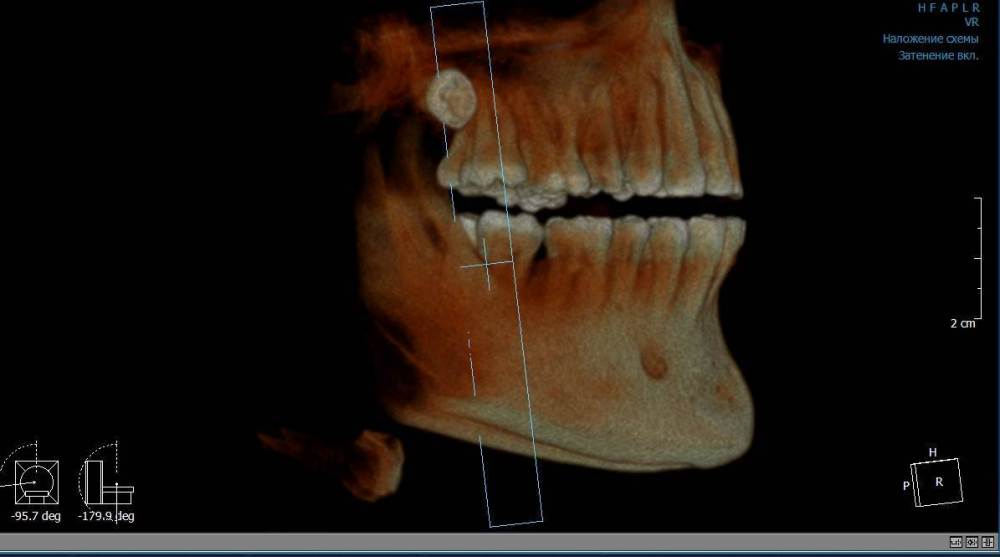

Mnrg Опубликовано 6 июля, 2023 Поделиться Опубликовано 6 июля, 2023 Всех приветствую! Беспокоит правосторонний гайморит и тонзиллит. Сделали КТ, нашли восьмерку, но предложили вместо удаления восьмерки депульпировать шестерку, консилиум сошелся во мнении, что корень перфорирует пазуху и пломба слишком близко к нерву, возможно воспаление. При зондировании между 6 и7 слегка побаливает десна, шестерка не беспокоит, холод чувствует, но не болит. Восьмерку предложили оставить. Спорить не стал, лишь решил собрать воедино мнения специалистов, т.к ближайшие более менее нормальные клиники от 100км. Архив с файлами КТ прикрепил, прошу специалистов глянуть и поделиться мнением, с чего все-таки начать, помочь разобраться.Archive.rar Ссылка на комментарий

wladdX Опубликовано 7 июля, 2023 Поделиться Опубликовано 7 июля, 2023 (изменено) Гайморит у вас совершенно необязательно имеет одонтогенную природу (вызван зубами). Судя по КТ, зуб 16 может быть виновником (а может и не быть). Для уточнения нужна также проверка витальности его пульпы (жив нерв или нет). Если пульпа нежизнеспособна, то этот зуб почти наверняка поддерживает воспалительный процесс в пазухе. Зуб 18 вряд ли нужно трогать. Лежит он себе в кости и пускай, никому он там не вредит. Да он вплотную прилежит к корням зуба 17, но и только. С внешней средой не контактирует. Никакого негативного влияния на соседние зубы он оказывать не должен: формирование корней завершено, потенции к росту и какому-либо движению нет. Удаление зуба 18 в данной ситуации вряд ли оправдано. Процедура не самая простая, но и не запредельной сложности. Изменено 7 июля, 2023 пользователем wladdX Ссылка на комментарий

Mnrg Опубликовано 7 июля, 2023 Автор Поделиться Опубликовано 7 июля, 2023 6 минут назад, wladdX сказал: Гайморит у вас совершенно необязательно имеет одонтогенную природу (вызван зубами). Судя по КТ, зуб 16 может быть виновником (а может и не быть). Для уточнения нужна также проверка витальности его пульпы (жив нерв или нет). Если пульпа нежизнеспособна, то этот зуб почти наверняка поддерживает воспалительный процесс в пазухе. Зуб 18 вряд ли нужно трогать. Лежит он себе в кости и пускай, никому он там не вредит. Да он вплотную прилежит к корням зуба 17, но и только. С внешней средой не контактирует. Никакого негативного влияния на соседние зубы он оказывать не должен: формирование корней завершено, потенции к росту и какому-либо движению нет. Удаление зуба 18 в данной ситуации вряд ли оправдано. Процедура не самая простая, но и не запредельной сложности. Шестерку проверяли холодом - чувствует, не знаю, означает ли это жизнеспособность пульпы, но на холод реагировал немного сильней других зубов. Сегодня открыл КТ программой RadiAntViewer и обнаружил в 3D просмотре визуальные признаки нахождения части восьмерки в краю пазухи. Конечно я не могу утверждать, т.к не врач и насколько понимаю это режим моделирования, но все же выглядит убедительно на мой скромный взгляд. Еще один глупый вопрос, если позволите) Возможно ли в шестерке в одном из трех корней воспаление и нерв разрушен, а другие два при этом будут создавать чувствительность, т.е быть "живыми" или же это фантастика? Деньги запросили немалые для нашего региона за депульпацию (13к) поэтому пытаюсь собрать как можно больше информации прежде, чем принимать решения. Ссылка на комментарий